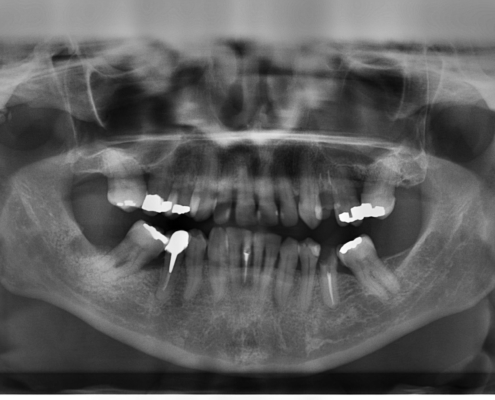

Eine gründliche Untersuchung, ein ausführliches Beratungsgespräch, in dem wir gerne alle Ihre Fragen beantworten, sowie eine transparente Therapie- und Kostenplanung im Falle einer Amalgamsanierung betrachten wir als Voraussetzungen für optimale Behandlungsergebnisse.

Amalgam ist auch heute in Deutschland noch das Füllungsmaterial Nummer eins, welches von den Krankenkassen als Regelversorgung im Füllungsbereich gilt.

Aber was ist Amalgam eigentlich, warum gehen hier die Meinungen so weit auseinander, warum wird es in einigen Praxen fast ausschließlich verwendet und in anderen gar nicht mehr, warum wird es täglich in etliche Zähne, also in den Körper eingebracht, muss aber als „Sondermüll“ entsorgt werden?

Hier wollen wir einige Fragen beantworten und Ihnen erläutern, wie wir mit Amalgamfüllungen, welche bei uns ausschließlich entfernt werden umgehen.